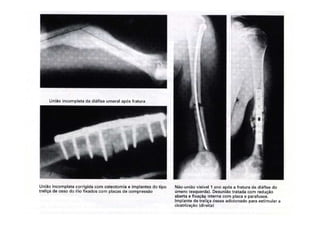

FRATURAS

Complicações:

- Consolidação viciosa

- Retardo de consolidação

- Não consolidação – Pseudo artrose

- Encurtamento

figura